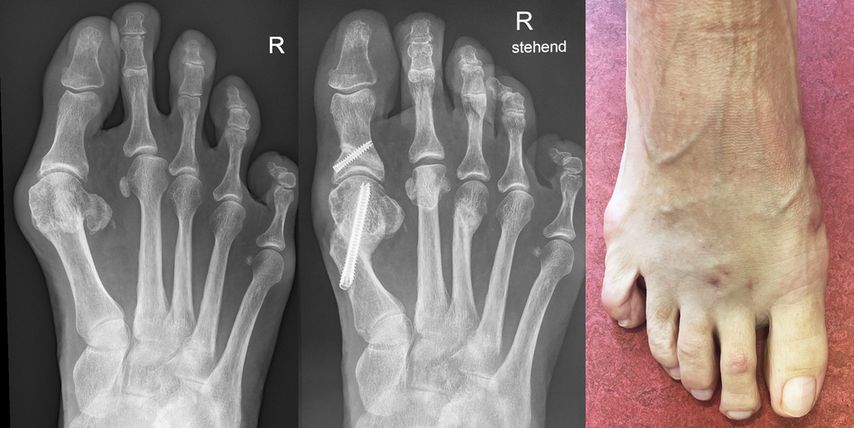

Unter der Generation 3 werden Modifikationen der Chevron-Osteotomie zusammengefasst, die per Stichinzision mittels Fräse durchgeführt werden. Fixiert wird mit kopflosen Schrauben. Redfern und Vernois bevorzugen hier sehr lange 3,5 mm- bzw. 4,0 mm-Schrauben, die von proximal medial am Metatarsale 1 in das Köpfchen eingebracht werden.2 Gerhard Kaufmann führt ebenfalls eine Osteotomie mit Fräse durch, fixiert aber weiter distal ähnlich wie bei der klassischen Chevron-Osteotomie (Abb. 1).

Vernois und Redfern präsentierten 100 Füße mit einem von 95% der Patienten als sehr gut und gut beurteilten Outcome.2 Gerhard Kaufmann publizierte 2020 seine Ergebnisse der minimalinvasiven Chevron-Osteotomie im Vergleich zur offenen Chevron-Osteotomie,6 mit Kontrollen nach 6 und 12 Wochen sowie 9Monaten und 5Jahren. Es gab keine Korrekturverluste zwischen den kurzfristigen und langfristigen Kontrollen, der Vergleich der Gruppen ergab keine Unterschiede. Jowett und Bedi analysierten 2017 die Lernkurve der minimalinvasiven Chevron-Osteotomie.7 Sie stellten eine steile Lernkurve fest. Palmanovich beschrieb 27 Patienten als notwendig, um die Lernkurve zu verlassen.8 Wenn die Technik beherrscht wird, so sind auch schwere Hallux-valgus-Fehlstellungen korrigierbar und vor allem Wundkomplikationen sind selten.